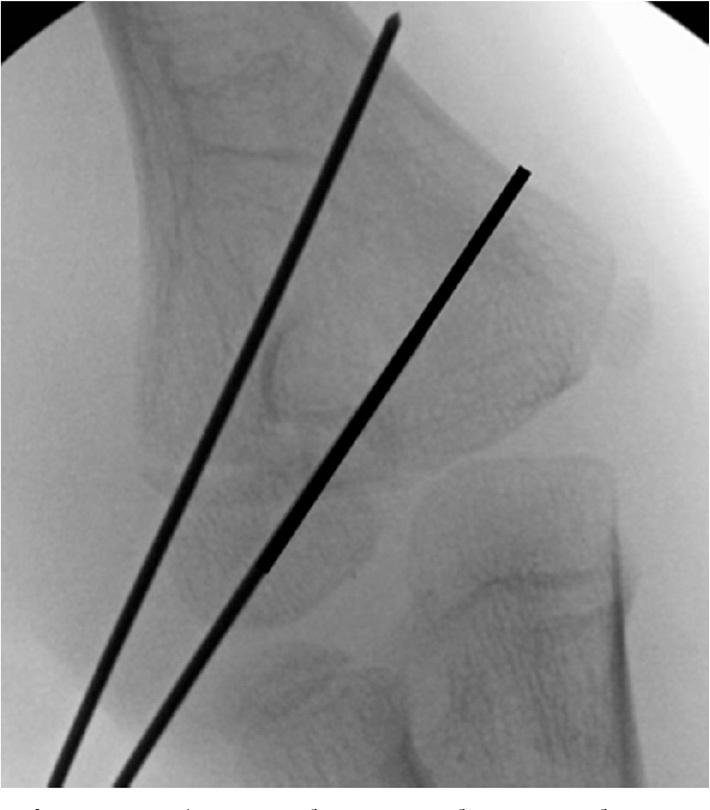

Lateral condyle fractures are the second most common elbow fracture in pediatric patients. Unlike supracondylar humerus fractures, these injuries involve the articular surface and present unique challenges. These injuries are graded based on the degree of displacement and this dictates your treatment. Both closed and open techniques are appropriate depending on the degree of displacement. Our preferred technique for open reduction and internal fixation is described and illustrated in the accompanying video. •Lateral condyle fractures are common elbow injuries in the pediatric population affecting the articular surface.•Accurate reduction of articular surface is critical.•In order to promote healing, these fractures often require longer immobilization than supracondylar fractures due to intraarticular nature of the injury.•Blood supply to the capitellum enters posteriorly, so one must be cautious with posterior dissection.

外侧髁骨折是儿科患者中第二常见的肘部骨折。与肱骨髁上骨折不同,这些损伤累及关节面并带来独特的挑战。这些损伤根据移位程度分级,这决定了治疗方式。根据移位程度,闭合和开放技术都适用。随附视频中描述并展示了我们首选的切开复位内固定技术。